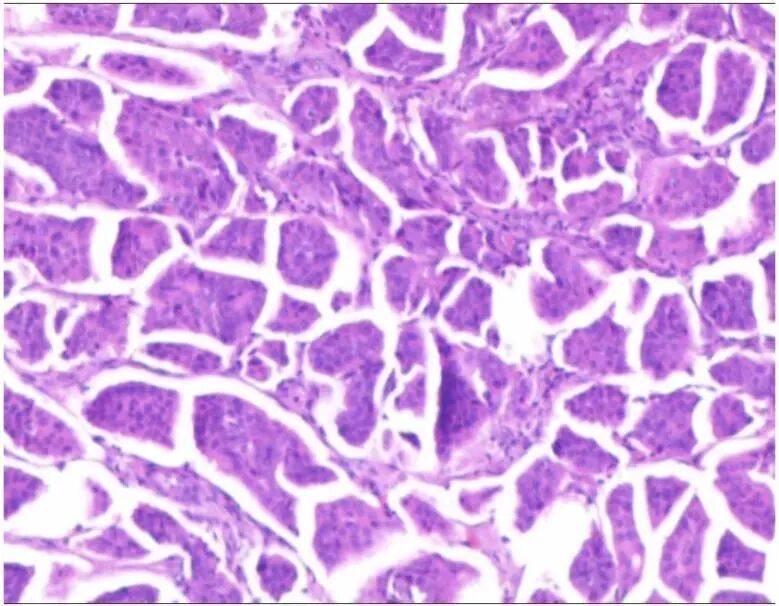

术后病理提示:右侧卵巢及右侧输卵管印戒细胞癌,对比回盲部切片,考虑肿瘤转移(图 8)。

图 8 手术病理提示印戒细胞癌转移